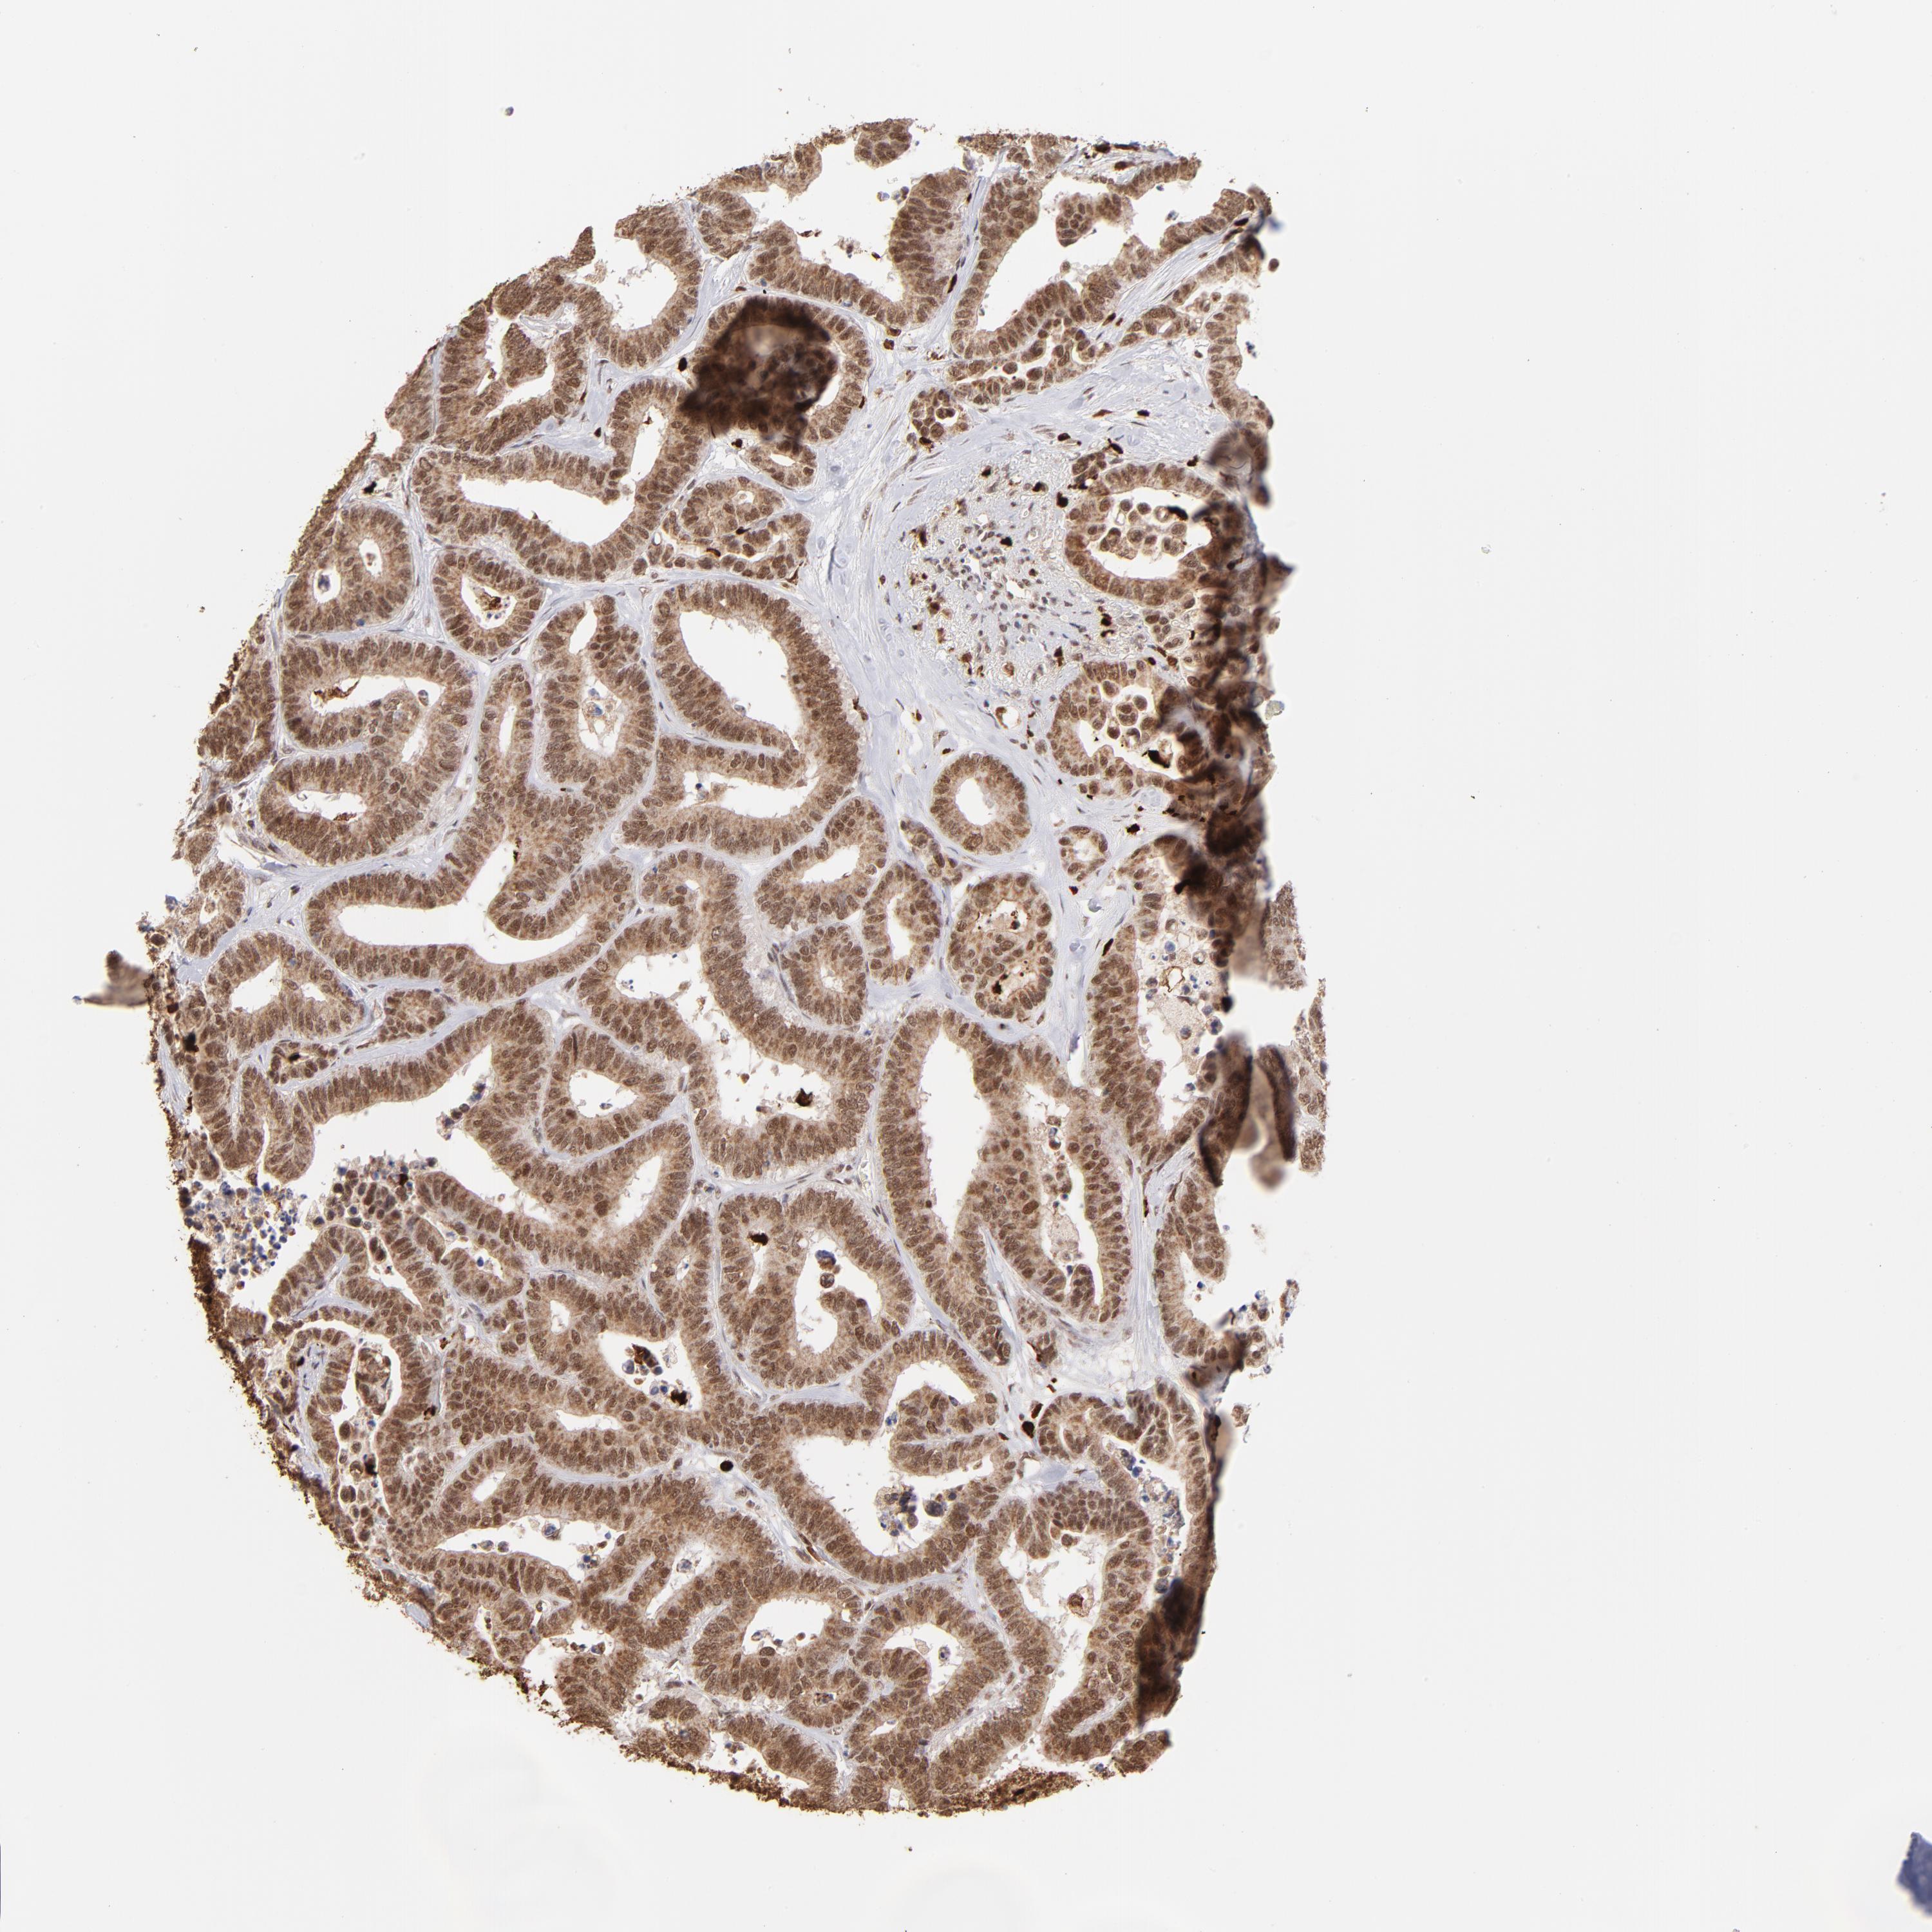

CANCER COLORECTAL CANCER Show tissue menu

Colorectal cancer

Human cancer

Colon adenocarcinoma